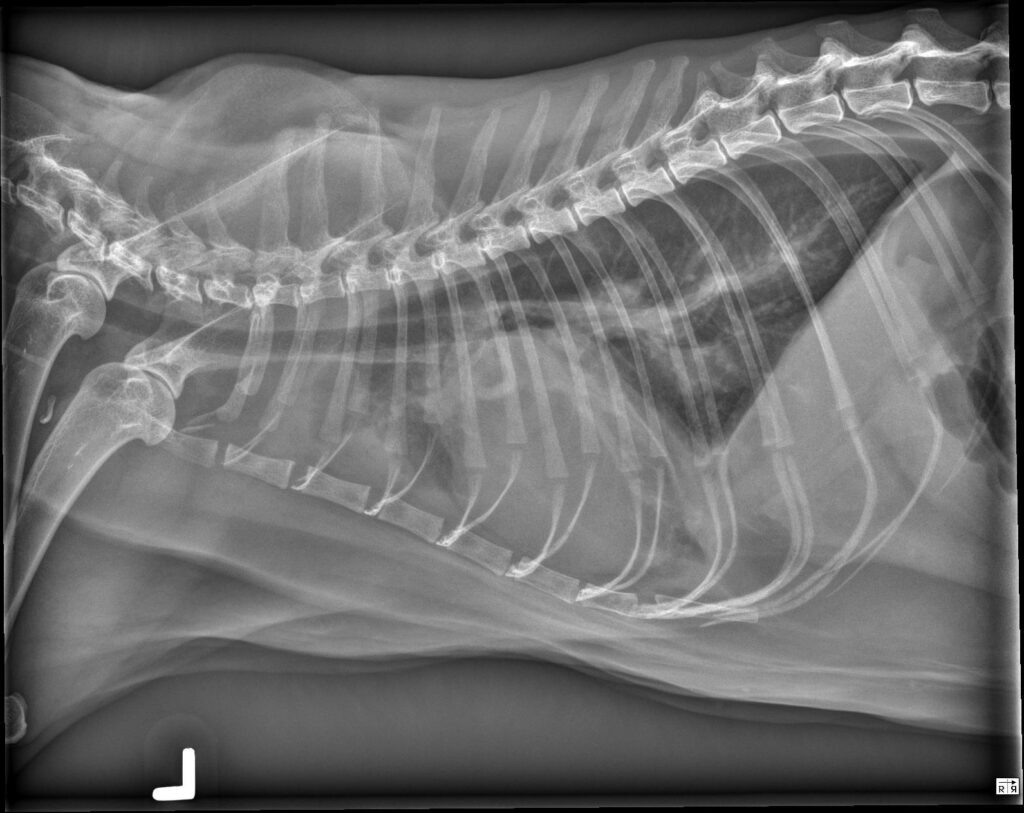

Radiology Quiz February 2026

History 2 year old labradoodle. Female Spayed. 2 weeks ago was diagnosed with aspiration pneumonia. Still lethargic.

...